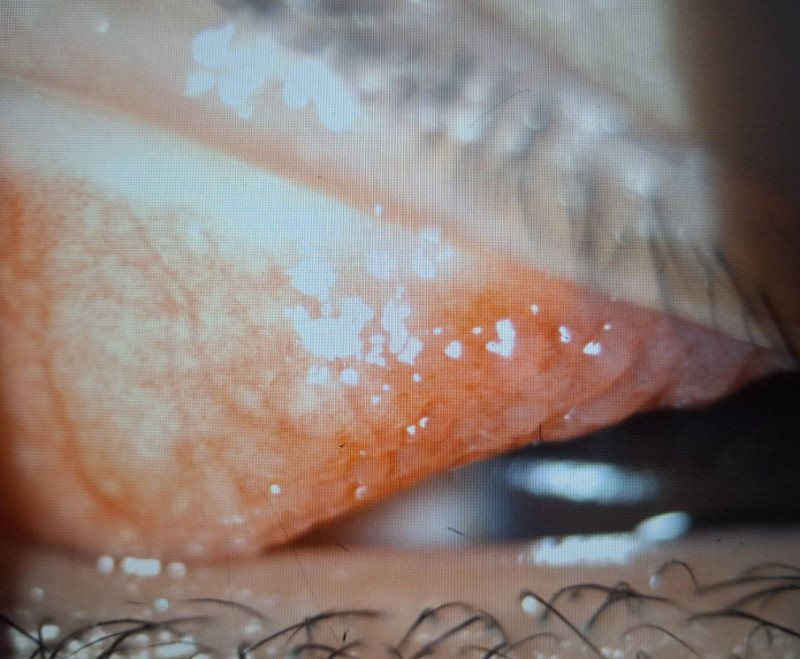

小二男童因長期眼睛癢揉眼,結膜炎導致左上眼瞼出現多顆巨大乳突。(洪啟庭提供)

男童因結膜慢性發炎,使結膜上皮細胞的過度增生,長成大於0.1公分的乳突。(洪啟庭提供)

巨大乳突壓迫不僅造成角膜潰瘍,還出現高度散光而視力模。(洪啟庭提供)